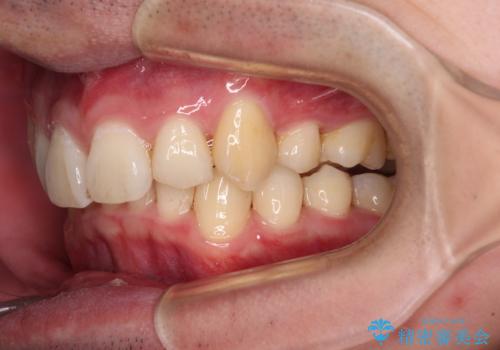

- 八重歯を気にして来院された患者様です。

顕著な上顎の八重歯とディープバイトであったため、上顎の左右第一小臼歯を抜歯することとしました。

犬歯歯根の位置や奥歯の咬み合わせから、ワイヤー装置での治療を強くおすすめいたしましたが、ご本人の強い希望により、妥協的な仕上がりとなることを了解いただき、インビザラインにて矯正治療を行うこととしました。

インビザライン単体で、左右ともに移動の難しい位置に歯根のある犬歯を整えるのは困難と判断し、補助装置を併用することとしました。